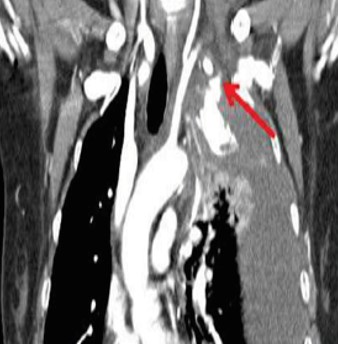

50歳代女性 腹痛、ショック:

• SMAの異常拡張

• 腸間膜主体に血腫

診断:SMA破裂を来した神経線維腫症1型